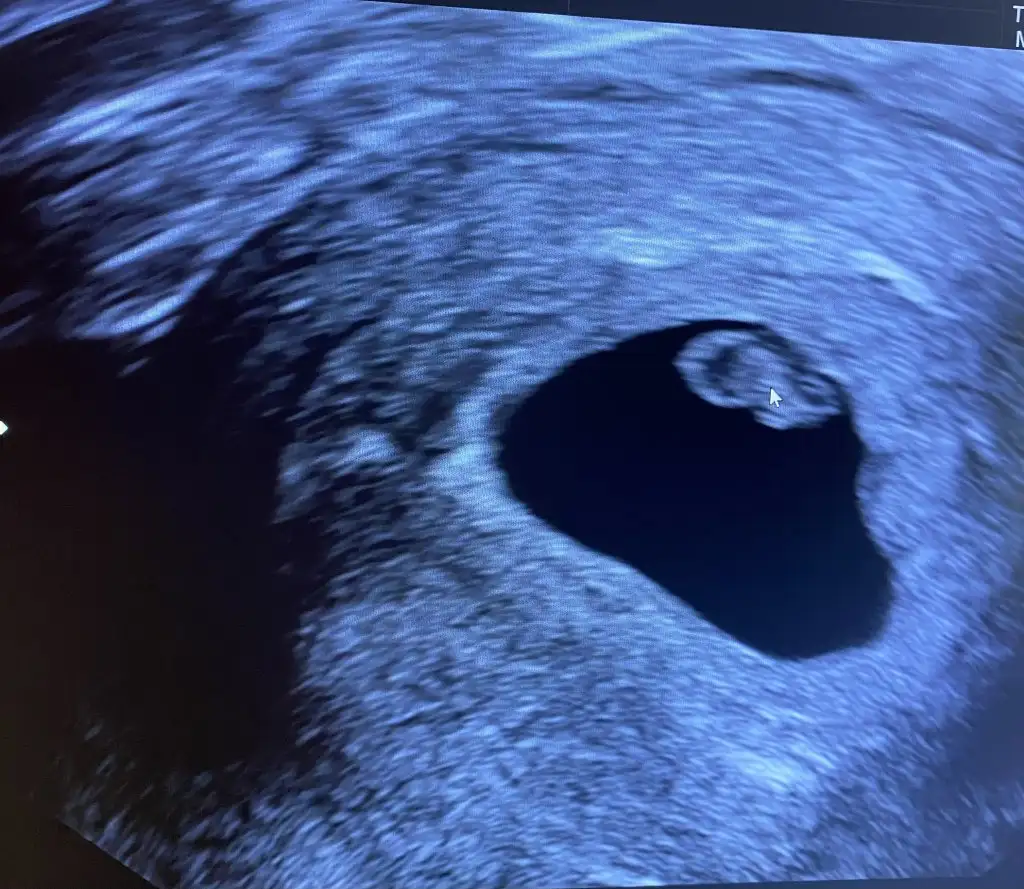

Kızlar selamlar, doktora geldim bugün sonunda 6 haftalık dedi. Sat 8 Nisan ama 4 Nisan olarak girdi usg ye göre gidelim dedi. Kesesi ve içinde bebek göründü. Kalp atışını dinletmedi ama kalbi de atıyor dedi. Bende durumlar bu şekil. Sizler nasılsınız